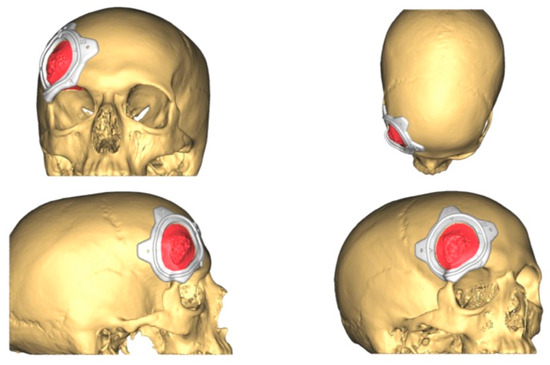

2.3.2. CAD-CAM Design of the PEEK Prosthesis

| 1 | 53/F | L/25 mm | Y | 4 mo | Dystopia | N | CT, MRI | Supraorbital rim, orbital roof | Intraosseous venous malformation | - | Resection + reconstruction | Y | Y | 1st, 2nd, 3rd | Coronal | Y | Piezoelectric device | N | PEEK prosthesis | 7 y/N |

| 2 | 54/F | R/33 mm | Y | 9 y | N | Y | CT, MRI | Frontal bone, orbital roof | Intraosseous venous malformation | - | Resection + reconstruction | Y | Y | 1st, 2nd, 3rd | Coronal | Y | Piezoelectric device | N | PEEK prosthesis | 6 y/N |

| 3 | 36/F | L/19 mm | Y | 6 mo | N | N | CT, MRI | Zygoma | Arteriovenous malformation | - | Resection + reconstruction | Y | Y | 1st, 2nd, 3rd | Transconjunctival + blepharoplasty + maxillary vestibular | Y | Piezoelectric device | N | PEEK prosthesis | 5 y/N |

| 4 | 47/M | L/30 mm | N | 2 y | N | N | CT | Zygoma | Intraosseous venous malformation | - | Resection + reconstruction | Y | Y | 1st, 2nd, 3rd | Transconjunctival + lateral canthotomy + maxillary vestibular | Y | Piezoelectric device | N | PEEK prosthesis | 6 y/N |